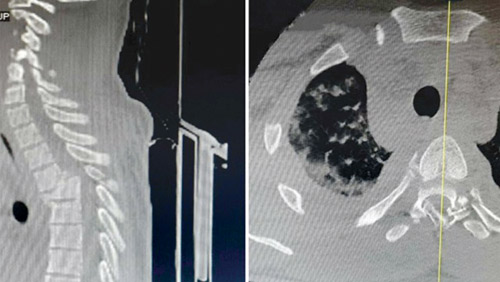

وبيّنت صور الأشعة المقطعية والمغناطيسية إصابة حادة في العمود الفقري، إضافة إلى كسر مركب في الفقرات الصدرية. وتسبب ذلك في الكثير من الأعراض شديدة التأثير أبرزها شلل شبه تام في الأطراف السفلية مع عدم القدرة على التحكم في التبول والبراز.

واستطرد د. المسعود قائلاً: ونسبة للتعقيدات الطبية التي اكتنفت الحالة تعامل الفريق الطبي معها بالسرعة اللازمة، وقرر التدخل الطبي العاجل، واتخاذ التدابير والتحضيرات اللازمة؛ إذ أُخضعت الحالة لعملية تحت المراقبة العصبية، تم فيها فك الضغط عن الحبل الشوكي، ومعالجة الكسر المركب، وتثبيت الفقرات في مكانها الطبيعي باستخدام تقنيتَي الشرائح المعدنية ذاتية الانغلاق، والبراغي المعدنية. وتعد الشرائح من أحدث تقنيات التعامل مع هذا النوع من الكسور. كما تم في العملية التي استغرقت «5» ساعات معالجة الأضرار التي لحقت بالعمود الفقري. وقد حققت العملية - والحمد لله - نجاحًا كبيرًا، وانعكس ذلك على الحالة الصحية للمريض التي تحسنت بعد العملية بشكل مطرد مع العناية الطبية الحثيثة أثناء الأيام القليلة التي ظل فيها منومًا بالمستشفى إلى أن غادرها إلى منزله وهو يتحرك على قدميه مع بعض المساعدة، والآن يقوم بتنفيذ برنامج إعادة تأهيل وعلاج طبيعي. وتشير المعطيات الطبية كافة إلى أنه سيستعيد بنهاية هذا البرنامج قدرته الكاملة على الحركة.